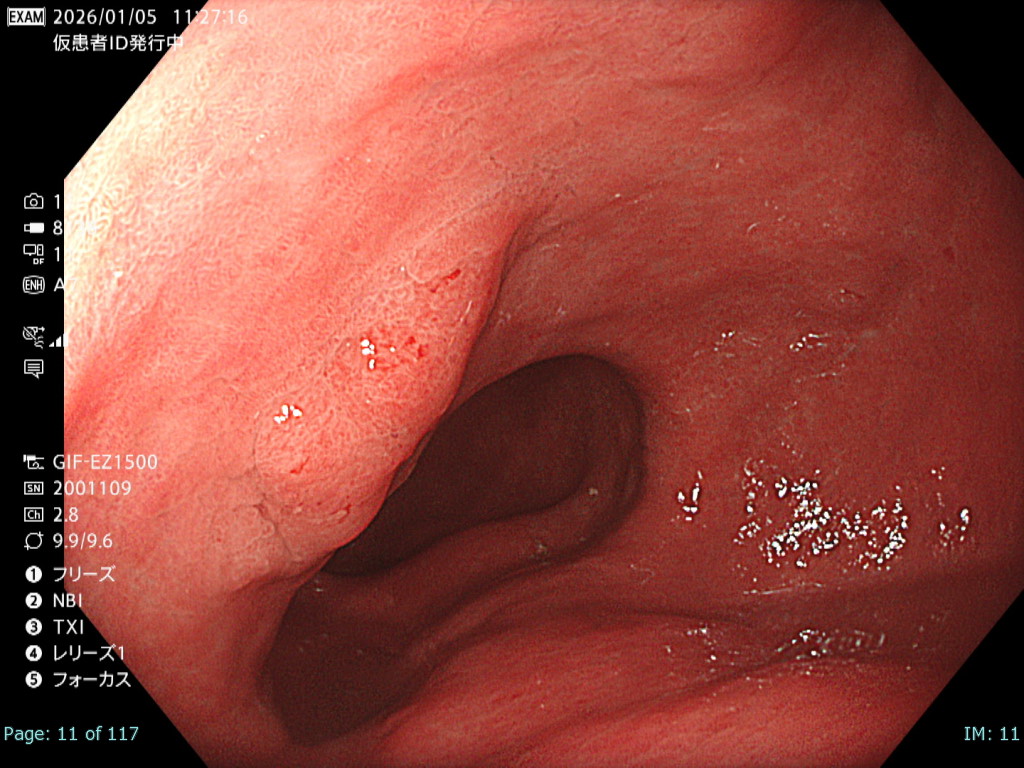

• 白色光観察①(近景)

強調設定:A7

図2

本病変は易出血性であり、血液洗浄後に観察・撮影できる時間は極めて短かったが、表面構造および色調を損なうことなく病変が明瞭に描出されている。記録画像として再評価にも十分耐え得る内視鏡画像である。

• 白色光観察②(中遠景)

図1

白色光非拡大観察では画面全体に良好なフォーカスが得られており、さらにBAI-MAC機能により深部まで十分な明るさが確保されている。そのため、2病変の性状および位置関係を正確に把握することが可能である。